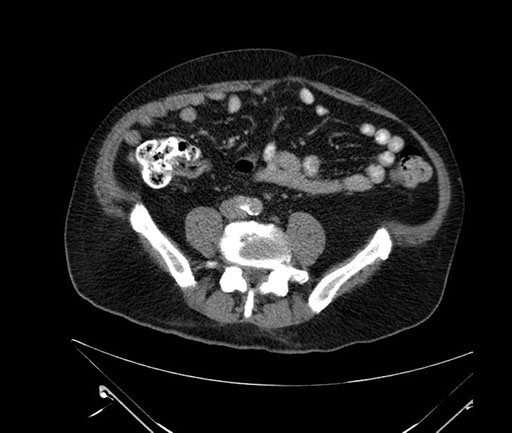

Imaging Analysis

Look through the patient's CT scan to identify any areas of concern for the necessary procedure.

Based on your CT findings, which issue(s) would give reason for "planned slowing down moment(s)" in this case?

Considering a standard Whipple procedure, what step(s) of the operation would you do differently in this case?